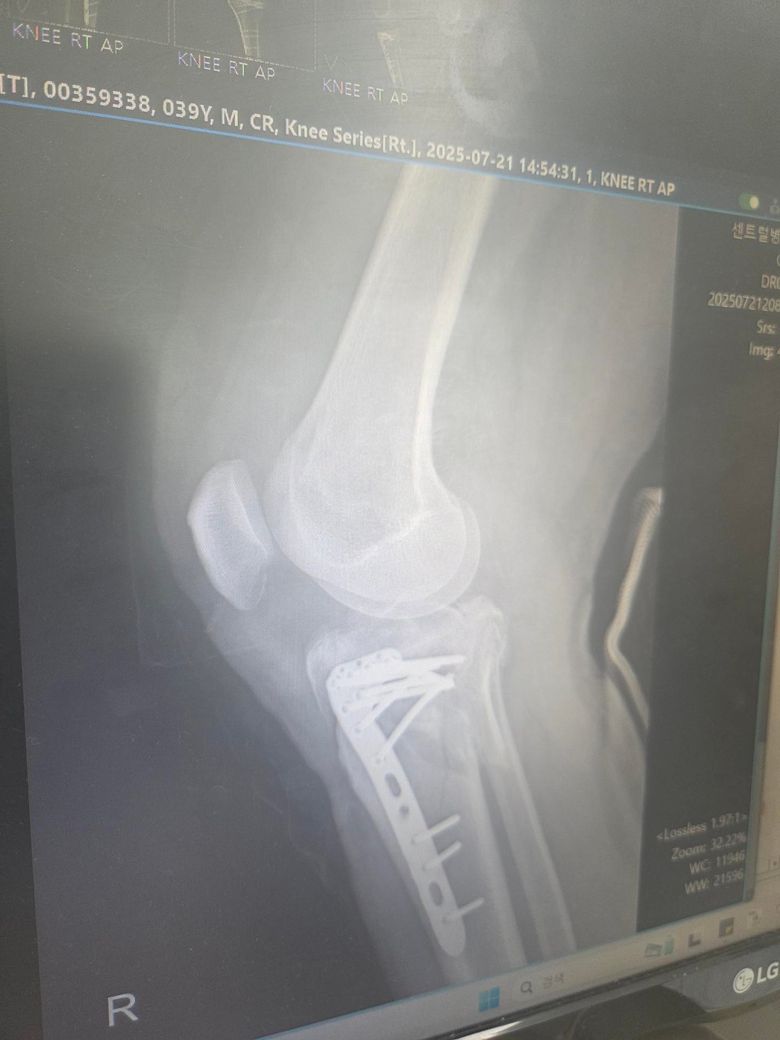

수술 후 3주차 엑스레이 사진 받아왔습니다.

• 2번 째 사진

분쇄골절 수술 후 3주차 엑스레이에서 뼈가 제 위치에 잘맞춰져 있고 금속 고정물이 안정적으로 유지된다면 수술은 성공적으로 이루어진 경우가 많습니다.

분쇄골절 이후 뼈의 정렬에 맞춰 고정이 잘 된 것으로 보이고 엑스레이상에서도 틀어짐이나 고정시 사용한 핀들이 제위치에서 크게 벗어나 있지는 않는 것으로 보입니다.

우선 현재 보여주신 엑스레이로는 분쇄 골절 된 부분은 핀으로 고정이 잘 된것으로 보여집니다.